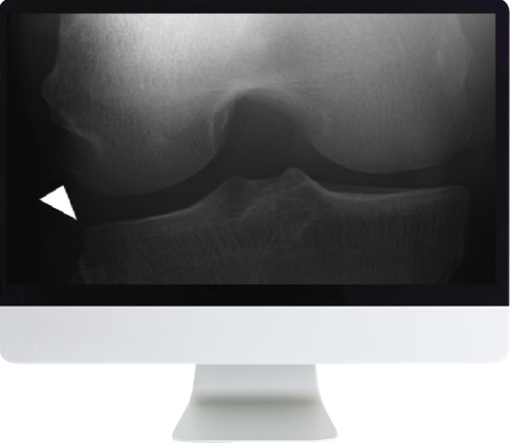

Musculoskeletal Imaging for the Practicing Radiologist 2018 (ARRS VIDEOS)

This course will provide a comprehensive and practical step-by-step framework for radiologists in a broad practice setting to establish and manage a variety of common musculoskeletal problems.

Ligamentous Inguries of the Knee: Analysis of MRI Footprints—D. Resnick

Meniscal Lesions in the Knee: Basics and Beyond—C. Chung